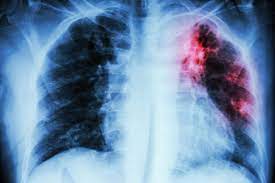

Eventos adversos de enfermedad pulmonar intersticial en hombres con cáncer de próstata que reciben terapia hormonal

Según este análisis de farmacovigilancia de FAERS, no se debe ignorar la asociación entre eventos de EPI y medicamentos de terapia hormonal, incluidos bicalutamida, flutamida, nilutamida, goserelina, degarelix y apalutamida, especialmente en la población japonesa. La función pulmonar de los pacientes con cáncer de próstata debe controlarse cuando reciben los medicamentos de terapia hormonal mencionados anteriormente, especialmente el primer año posterior a la medicación. Br J Clin Pharmacol 29 de marzo de 2022